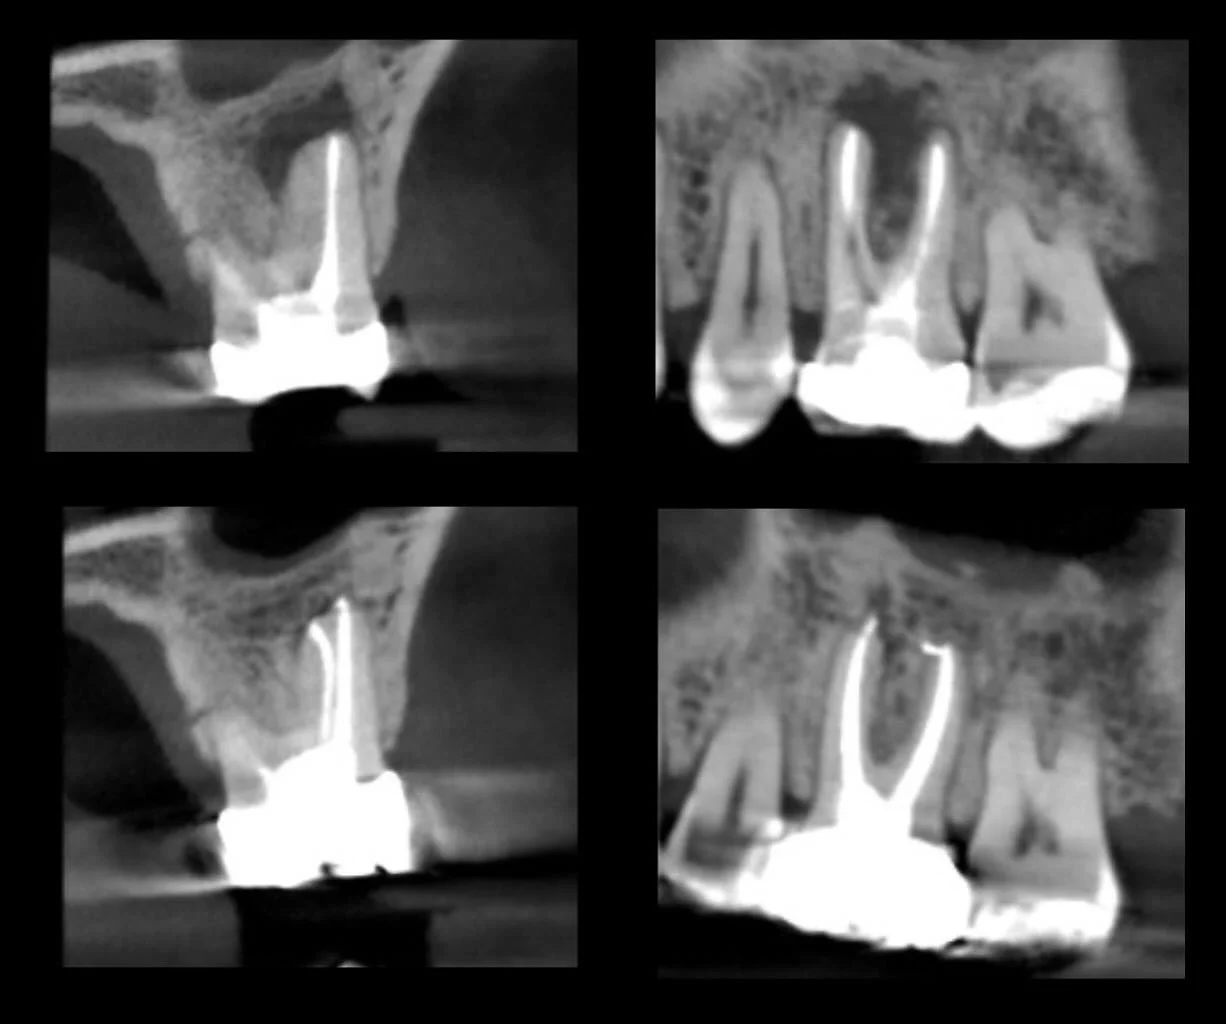

I am a board-certified endodontist with advanced specialty training and an academic interest in diagnostic reasoning, retreatment, and microsurgical endodontics. My work emphasizes CBCT-guided decision-making, interdisciplinary collaboration, and evidence-based care in complex clinical scenarios.

Board certification in endodontics represents an advanced level of professional achievement beyond specialty training. It is a voluntary, multi-year process that requires successful completion of a comprehensive written examination and rigorous peer review of complex clinical cases, evaluating diagnostic judgment, technical execution, and long-term outcomes. Less than 25% of practicing endodontists achieve board certification, reflecting a commitment to clinical excellence, continual self-assessment, and the highest standards of the specialty.